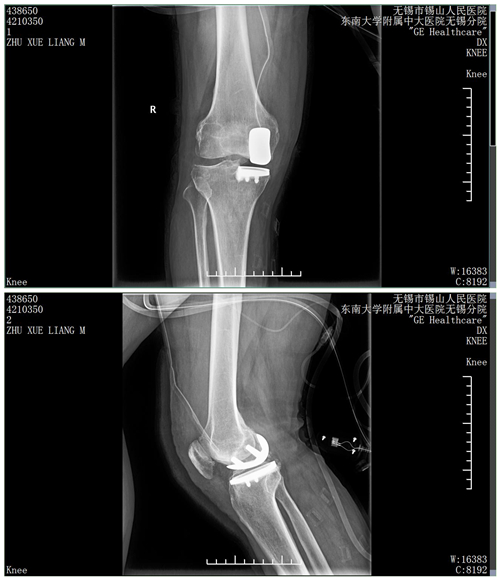

术中,在东南大学附属中大医院王宸教授的指下,倪英杰主任主刀,马颜主治医师、张栋医师配合,仅用时1小时,成功为患者实施了右膝关节单髁置换术。在骨科医护人员的指导下,术后当天患者卧床即行股四头肌等长收缩练习及膝关节屈伸练习,第二天患者就可以下床负重行走,疼痛感消失,术后恢复良好。手术良好的效果也得到患者和家属的连连称赞。

据骨科副主任倪英杰介绍,骨和关节组织会随着年龄的增长发生退行变化,尤其好发于承重的关节和多活动的关节。此次开展的膝关节单髁置换术是相对全膝关节置换术而言的一种新型微创手术,只置换病损部位,对膝关节内侧或外侧间室进行表面置换,用以替代膝关节股、胫关节损坏的软骨表面,该技术不需要去除前后交叉韧带,最大限度的保留了患者的本体感觉和关节功能。与传统传统手术相比,该手术切口小,患者承受的痛苦小,有利于术后关节功能的快速恢复。(图文/张栋 编辑/孙炜 审核/杨居艳) |